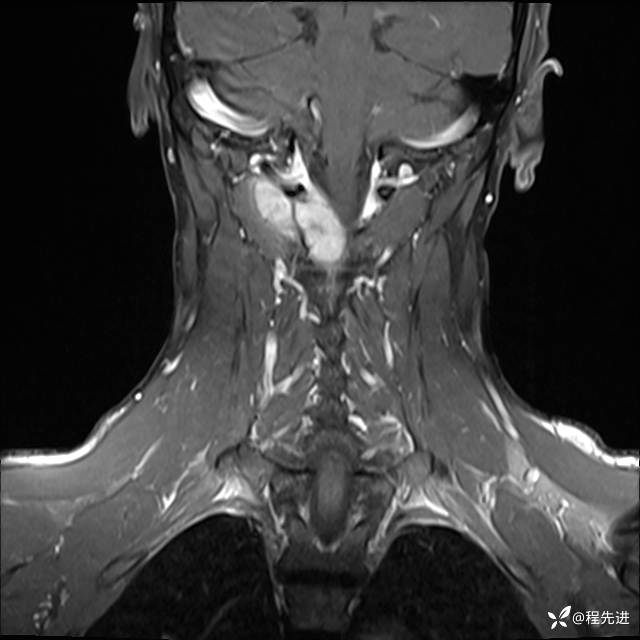

MRI平扫+增强:

T1增强: